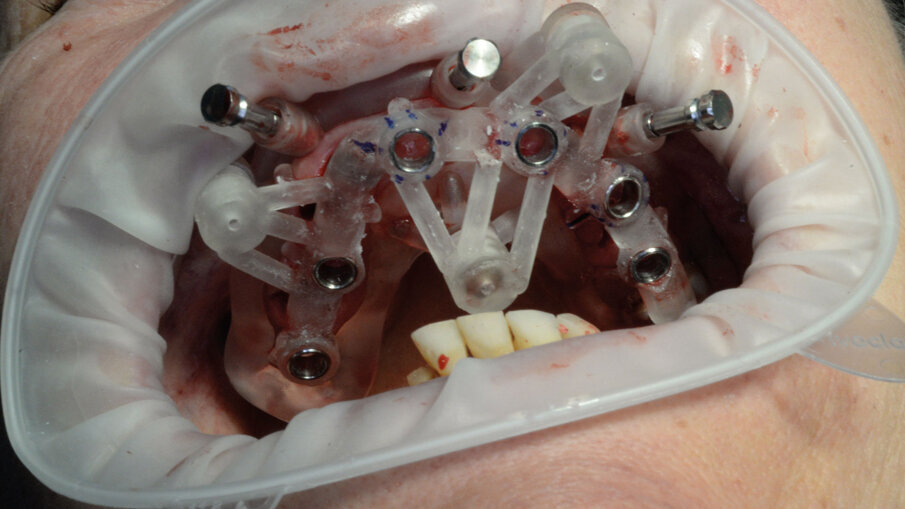

Per la realizzazione delle dime chirurgiche abbiamo utilizzato il nuovo modulo Sculpt rilasciato per lo stesso software di chirurgia guidata BNX 3D GUIDE. Questo nuovo modulo permette di creare una serie di dime scomposte da utilizzare in sequenza per eseguire le estrazioni e l’osteoplastica necessaria, rimanendo sempre all’interno di un flusso di lavoro guidato. Le dime si adattano l’una all’altra grazie a supporti di accoppiamento che contengono piccoli magneti con polarità opposta. L’azione di questi magneti permette di ritrovare velocemente e fedelmente sempre la stessa posizione delle dime anche se dovessimo rimuoverle per poi reinserirle. Affidandoci alla stabilità ancora presente su alcuni denti abbiamo progettato una prima dima ad appoggio dentale che permettesse il corretto posizionamento della dima esterna che sarà l’unica a rimanere sempre in posizione fino alla fine dell’intervento (Fig. 9). Una volta stabilizzata con i pin di stabilizzazione e rimosso il posizionatore, si è potuto apprezzare la bellezza della metodica che permette un’ampia visione e molto spazio a disposizione per poter eseguire le fasi chirurgiche preliminari di preparazione (estrazioni e sollevamento di piccoli lembi). Liberata l’arcata dall’ingombro dei denti e di tessuti in eccesso si è potuto posizionare la dima di perforazione nella corretta posizione grazie alla presenza della dima esterna rimasta in posizione (Figg. 10-13).

Alla preparazione dei tunnel implantari è seguito il loro inserimento sempre con tecnica guidata utilizzando gli appositi montatori forniti nel kit, avendo cura di far combaciare le tacche di riferimento dei montatori con le linee di repere preventivamente disegnate sulla dima così da ottenere il corretto posizionamento dei 2 mua angolati previsti nel settore anteriore (Fig. 14). In fase chirurgica il posizionamento dei mua è stato ulteriormente facilitato dalla presenza di un doppio esagono presente all’interno dell’impianto che rende possibili ulteriori aggiustamenti “di fino” del componente protesico. Avvitate tutte le torrette il provvisorio è stato poi cementato con cemento duale dedicato utilizzando un foglietto di diga preforato per facilitarne la cementazione (Figg. 15, 16).